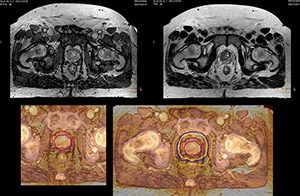

“Using MR, the prostate is well delineated. We quickly see the edges of cancerous tumors like in prostate cancer, and as normal structures can be defined, we can optimize the treatment plan to protect these organs and their normal function. This can potentially improve the outcome. And it improves workflow as well. We can contour more quickly, confident that the tumor is going to be in the field.”

“When a patient registers, first CT simulation and MR simulation are done, followed by CT-MR registration on Pinnacle3. Then the target and normal organ delineation is performed on MR images. Meanwhile we create a reference CT image for online treatment and localization correction. During the treatment phase we can perform additional MRI scans to visualize the anatomy changes and create an adaptive plan. This plan basically adapts the treatment plan to the changes.”

“I think that in the future functional information from MRI is going to become much more important, both for prognostic and predictive measures, as well as for treatment response measures,” Dr. Stevens concludes. “With Ingenia MR-RT we will have the ability in our department to make decisions based on, for instance, changes in blood flow and diffusion at the beginning, middle and end of treatment. I believe that over time, every large cancer center will need to have an MR scanner in their radiation oncology department.”